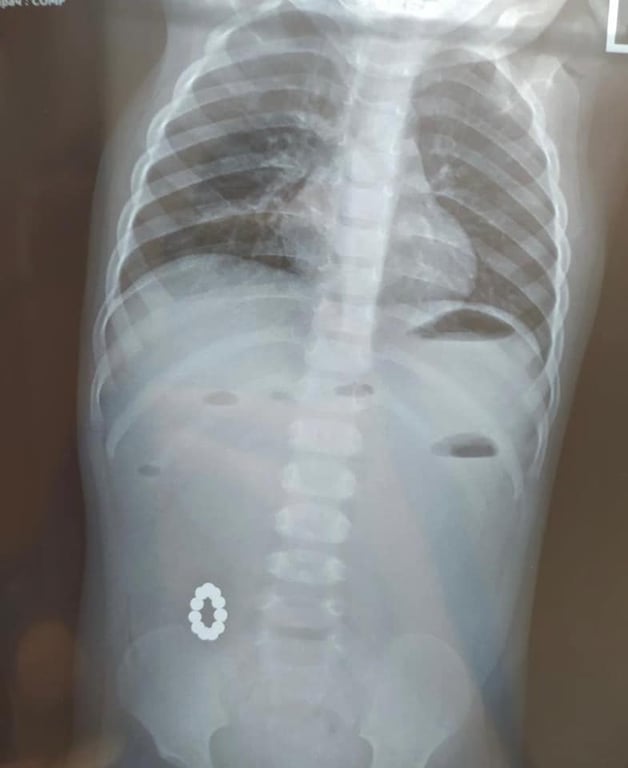

У Харкові однорічна дівчинка проковтнула магніти. Декілька кульок з’єднались між собою у кишківнику дитини та утворили кільце. Дівчинку оперативно прооперували.

Однорічну дівчинку було шпиталізовано. Спершу була підозра на харчове отруєння. Однак у ході більш детальної діагностики лікарі знайшли у кишківнику дитини небезпечні предмети. Як виявилось, дівчинка проковтнула магніти. Всередині кульки з’єднались, утворивши кільце, та призвели до патології – непрохідності кишківника.

Дівчинці провели складну операцію та видалили магніти. Хірургічне втручання пройшло успішно. Непрохідність було ліквідовано.

"Черговою медичною бригадою у складі дитячих хірургів Ярослава Дєгтярова, Ігоря Чорномаза, лікаря інтерна Оксани Вітренко, дитячого анестезіолога Євгена Вiштала, операційної сестри Оксани Арцибашевої було успішно виконане складне оперативне втручання: видалені сторонні тіла та ліквідована непрохідність кишкового шляху", – повідомили у лікарні.